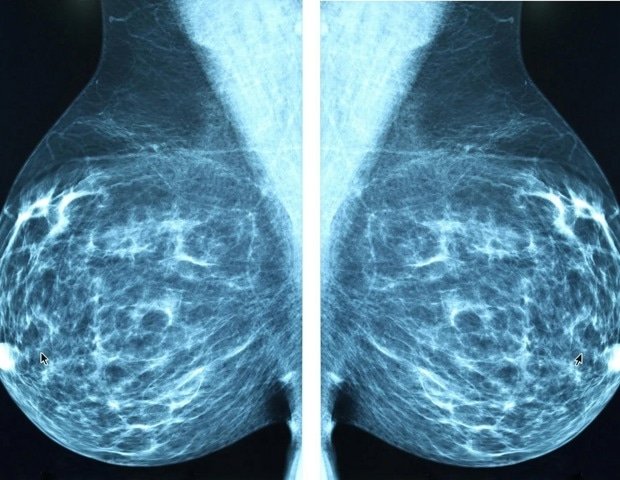

New guidance from the American College of Physicians (ACP) says all asymptomatic, average-risk women between the ages of 50 and 74 should undergo a mammogram every other year for breast cancer. Women ages 40 to 49 should discuss their breast cancer risks and the benefits and harms of screening with their doctors. This is because the harms of screening, such as false-positive results, resulting psychological distress, overdiagnosis, overtreatment, additional testing, and radiation exposure, may outweigh the uncertain benefits in this population. ACP’s advice, “Breast Cancer Screening in Asymptomatic Average-Risk Adult Women: Guidance Statement from the American Medical Association,” Annals of Internal Medicine.

The ACP also provides guidance on when to stop breast cancer screening and how to approach screening for women with dense breasts. ACP says women over 75 who are asymptomatic and at average risk or who have a limited life expectancy should talk to their doctors about stopping routine screenings. This is because the benefits of screening are diminished or uncertain beyond age 74, while potential harms such as overdiagnosis are more likely to occur with increasing age. ACP advises physicians to consider additional digital breast tomosynthesis (DBT) for asymptomatic average-risk women with dense breasts. Decision-making must consider potential benefits and harms, radiation exposure, availability, patient values and preferences, and cost. However, the ACP advises against using adjunctive MRI or ultrasound to screen this population.